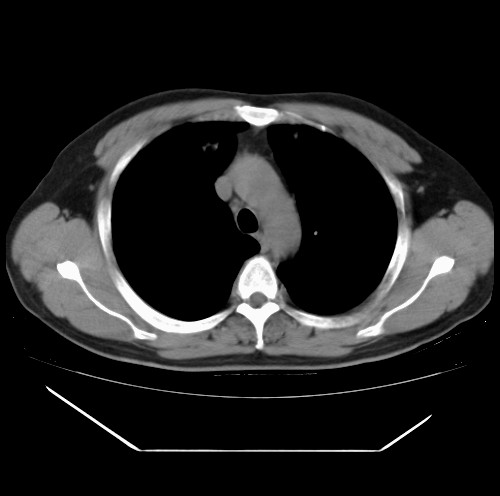

标题: CT22085:双肺多发结节

男,44岁,咳嗽,痰中带血2天。

病灶大部分位于胸膜下,结节大小相差不是很大,肺尖太干净。这种结核没见过,我认为可排除。

首先考虑转移,不除外肉芽肿、真菌感染。建议查其它。

除肺内及胸膜下可见多发大结节外,在肺小叶中心核、小叶间隔及支气管血管束上亦可见多方小结节,可以认为是随机分布。考虑转移可能性大。

仔细观察病灶形态,病灶边界部分清楚,结合临床症状,首先考虑转移,纵隔内多个肿大淋巴结影。

双肺血管纹理末端多发类圆形结节,边界光滑清晰 气管前腔静脉后淋巴结肿大

考虑转移瘤

沿血管分布,位于血管末端。转移瘤多见,血行性菌栓也可见到。

本例双肺多发类圆形高密度灶,边清,结合病史多考虑双肺多发转移改变,可以结合实验室检查。